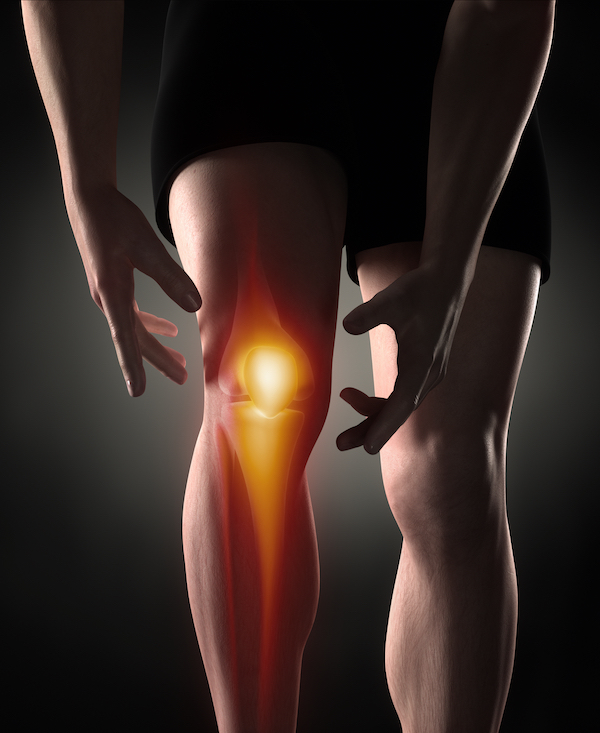

Have you had an injury or medical event, and you have found you haven't been treated as quickly as you expected, with the result you are now living with some level of permanent impairment?

Over the years, this situation has arisen regularly, prompting some interesting responses from our medical and health systems.